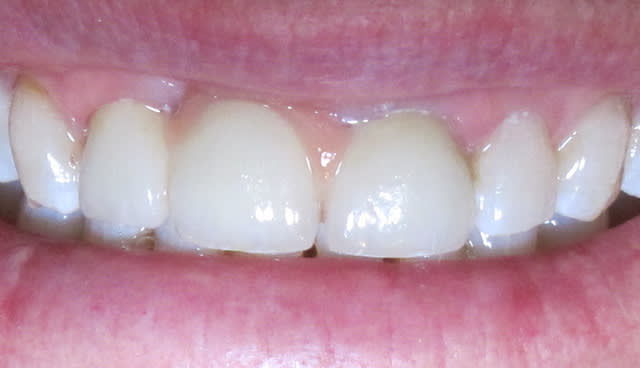

Img 5804 rvn38o - Eugenol

Img 5813 bhh1tm - Eugenol

Img 5820 kowclt - Eugenol

Img 5815 gymgib - Eugenol

Img 5816 okgijh - Eugenol

J'aurai bien aimé une photo sans l'amovible, mais à mon avis il était possible de faire autre chose qu'une fausse gencive céramique moche.

L'état paro du bas est super moche.

La 21 aurait du être allongée apicalement, elle est moins longue que la 12...

le problème ici sont les embrasures effectivement.

2 les dents sont assez peu hautes, on pourrait en profiter pour faire des élongations coronaires sur les incisives.

Ces 2 éléments conjugués auraient peut etre pu supprimer la ceram rose...

La 21 a été retouchée après la photo